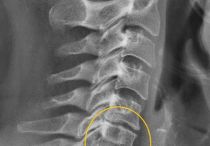

Как лечить растяжение мышц шеи: причины, симптомы и методы лечения

Признаки и симптомы растяжения шейных мышц: клиническая картина, основные методы медикаментозной терапии, физиотерапии и ЛФК. Особенности реабилитации.